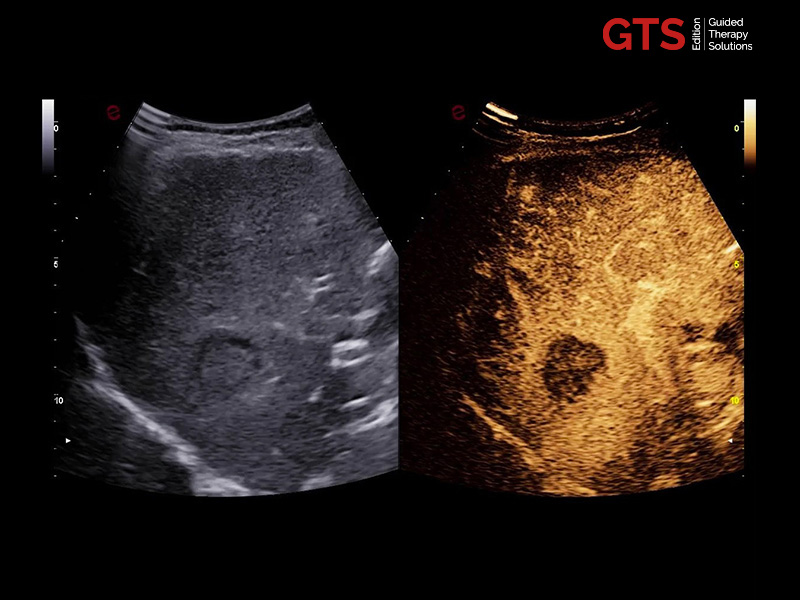

CnTI™ is Esaote’s CEUS technology that helps to identify suspicious areas in the prostate, helping to target areas to be biopsied. Furthermore, it can be used for focal therapy follow-up.

The CnTI™ guarantees a very high sensitivity in detecting contrast media agents, while maintaining long persistence of the contrast bubbles.

CnTi™ (Prostate perfusion study - Suspected anterior lesion)